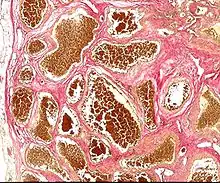

| Histology of a cavernous hemangioma | |

Cerebral cavernous malformation (CCM) is a cavernous hemangioma that arises in the central nervous system. It can be considered to be a variant of hemangioma, and is characterized by grossly large dilated blood vessels and large vascular channels, less well circumscribed, and more involved with deep structures, with a single layer of endothelium and an absence of neuronal tissue within the lesions. These thinly walled vessels resemble sinusoidal cavities filled with stagnant blood. Blood vessels in patients with cerebral cavernous malformations (CCM) can range from a few millimeters to several centimeters in diameter. Most lesions occur in the brain, but any organ may be involved.[1]